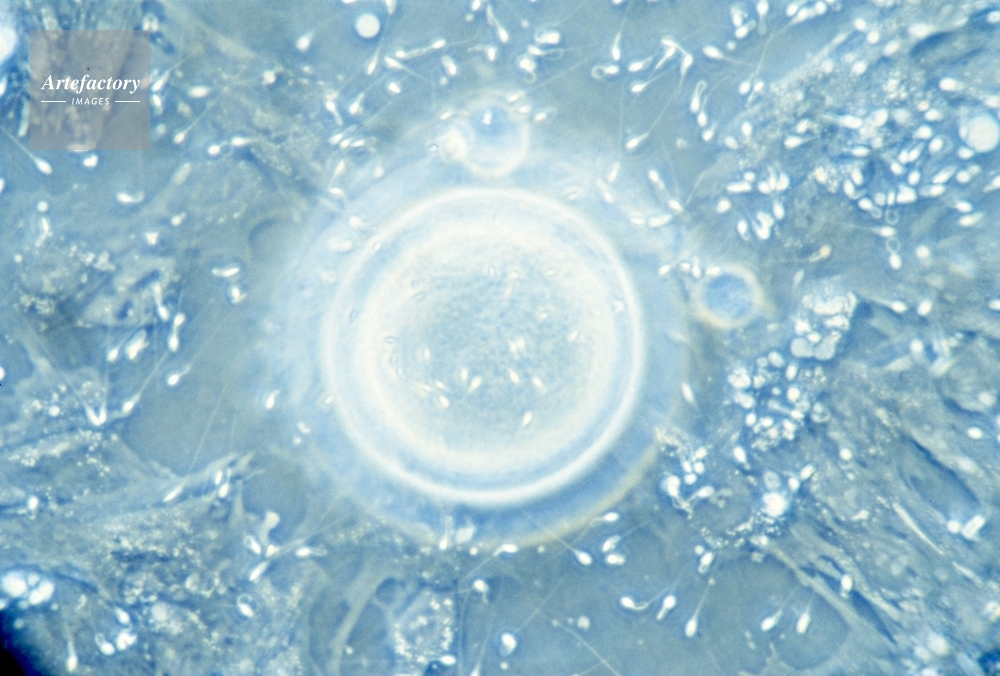

| 作品タイトル | 卵子に群がる精子〔ヒト〕 | モデルリリース | なし | |